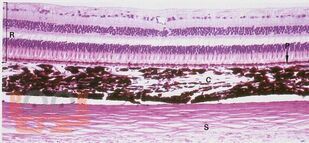

В учебном пособии представлен материал по развитию, строению и функции зрительного анализатора (органа зрения). Пособие содержит контрольные тестовые задания, позволяющие закрепить усвоение сложных вопросов, касающихся строения органа зрения.